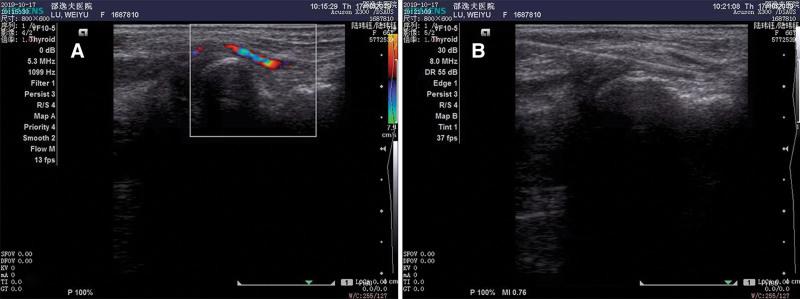

Regarding the site of arterial access during the intervention, transracial intervention can reduce the risk of bleeding and vessel-related complications as well as improve patient comfort. Importantly, the distal radial artery (DRA) approach may reduce the incidence of radial artery occlusion and digital ischemia, but the feasibility and safety of DRA in performing subdiaphragmatic vascular interventions remain unclear. From January 2018 to December 2019, 106 patients were admitted to our department for visceral angiography and intervention by left distal radial artery accessing in an anatomical snuffbox. In total, 152 times of vascular interventions were performed during this period. Patients demographics, procedure details, technical success, and access site-related complications were recorded and evaluated. The mean age was 58.9 (range 22-86) years. Males accounted for 80.2%. Thirty-five patients (33%) had 2 or more procedures via the DRA approach. Technical success was achieved for 96.1% of procedures (146 cases) and 3.9% of cases failed to perform the intended procedure via the DRA approach (6 cases). The 4-Fr sheath was used in 86.8% of cases, and the 5 Fr sheath was used in the rest of the 13.2% of procedures. The rate of asymptomatic radial artery occlusion was 5.7% (6 of 106 patients). No patient suffered from distal limb ischemia after a long-time follow-up. Eight patients suffered postoperative local pain, transient numbness, or local bruised in the anatomical snuffbox without major complications. Patients with postoperative complications recovered quickly by using nonsteroidal anti-inflammatory drugs or without further treatment. Left distal radial artery access is safe and feasible as a new technique for visceral angiography and intervention.

关于介入治疗中的动脉入路部位,经皮桡动脉入路可降低出血和血管相关并发症的风险,并提高患者舒适度。重要的是,远端桡动脉(DRA)入路可降低桡动脉闭塞和手指缺血的发生率,但 DRA 行膈下血管介入的可行性和安全性尚不清楚。2018 年 1 月至 2019 年 12 月,我院采用桡动脉入路行解剖学鼻烟窝内左侧远端桡动脉入路对 106 例患者行内脏血管造影和介入治疗。在此期间共进行了 152 次血管介入治疗。记录并评估了患者的一般资料、手术细节、技术成功率和入路相关并发症。患者的平均年龄为 58.9 岁(范围 22-86 岁)。男性占 80.2%。35 例(33%)患者通过 DRA 途径进行了 2 次或更多次操作。96.1%(146 例)的手术达到了技术成功,3.9%(6 例)的手术因 DRA 途径无法进行预期的手术而失败。86.8%的病例使用了 4Fr 鞘,其余 13.2%的病例使用了 5Fr 鞘。无症状桡动脉闭塞的发生率为 5.7%(106 例患者中有 6 例)。长期随访无患者发生远端肢体缺血。8 例患者术后出现局部疼痛、短暂麻木或解剖学鼻烟窝局部瘀伤,但无重大并发症。术后并发症患者使用非甾体抗炎药或无需进一步治疗后很快恢复。作为一种新的内脏血管造影和介入技术,左侧远端桡动脉入路是安全可行的。